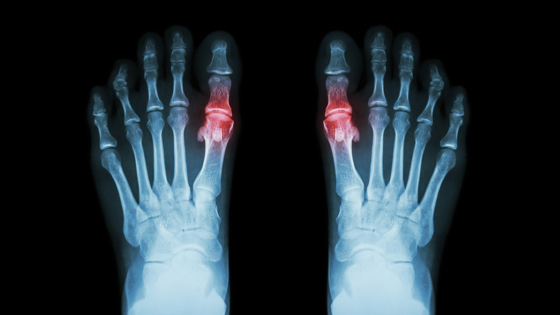

Подагра возникает, когда в крови повышается уровень мочевой кислоты, из которой образуются острые кристаллы. Они оседают в суставах, вызывая сильную боль, отёк и воспаление. Долгое время болезнь считалась результатом вредного образа жизни — переедания, злоупотребления алкоголем и малоподвижности. Однако ученые подчеркивают, что это ошибочное представление.

Исследователи сравнили ДНК 120 295 человек с подагрой и данных более 2,5 миллиона здоровых людей. В результате они выявили 377 участков генома, связанных с болезнью, из которых 149 ранее никогда не связывали с подагрой. Эти результаты подтверждают, что гены участвуют сразу в нескольких важных процессах: они влияют на способность организма выводить мочевую кислоту и определяют, насколько активно иммунная система реагирует на её кристаллы, вызывающие воспаление суставов.